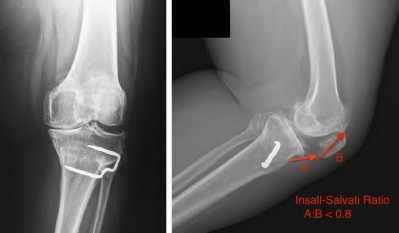

A 65-year-old woman with painful knee arthritis and the deformity seen in Figure A, is scheduled to undergo a total knee arthroplasty. All the following are risk factors for a post-operative peroneal palsy EXCEPT:

Figure A demonstrates and AP radiograph of the knee showing end-stage arthritis with severe lateral compartment narrowing.